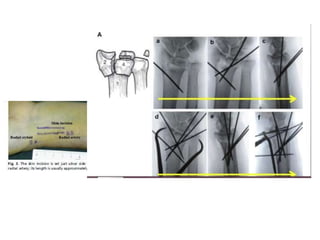

Reducción con clavos percútaneos

• Colocacion de clavos percutaneos

• Se introducen por la apofisis estiloides del radio

• Se utilizan clavos kirschner 1.5 mm

• Se coloca yeso por 3- 4 semanas

D. Green Cirugía de mano vol 1, Marban, España, 2007

Kapadnji